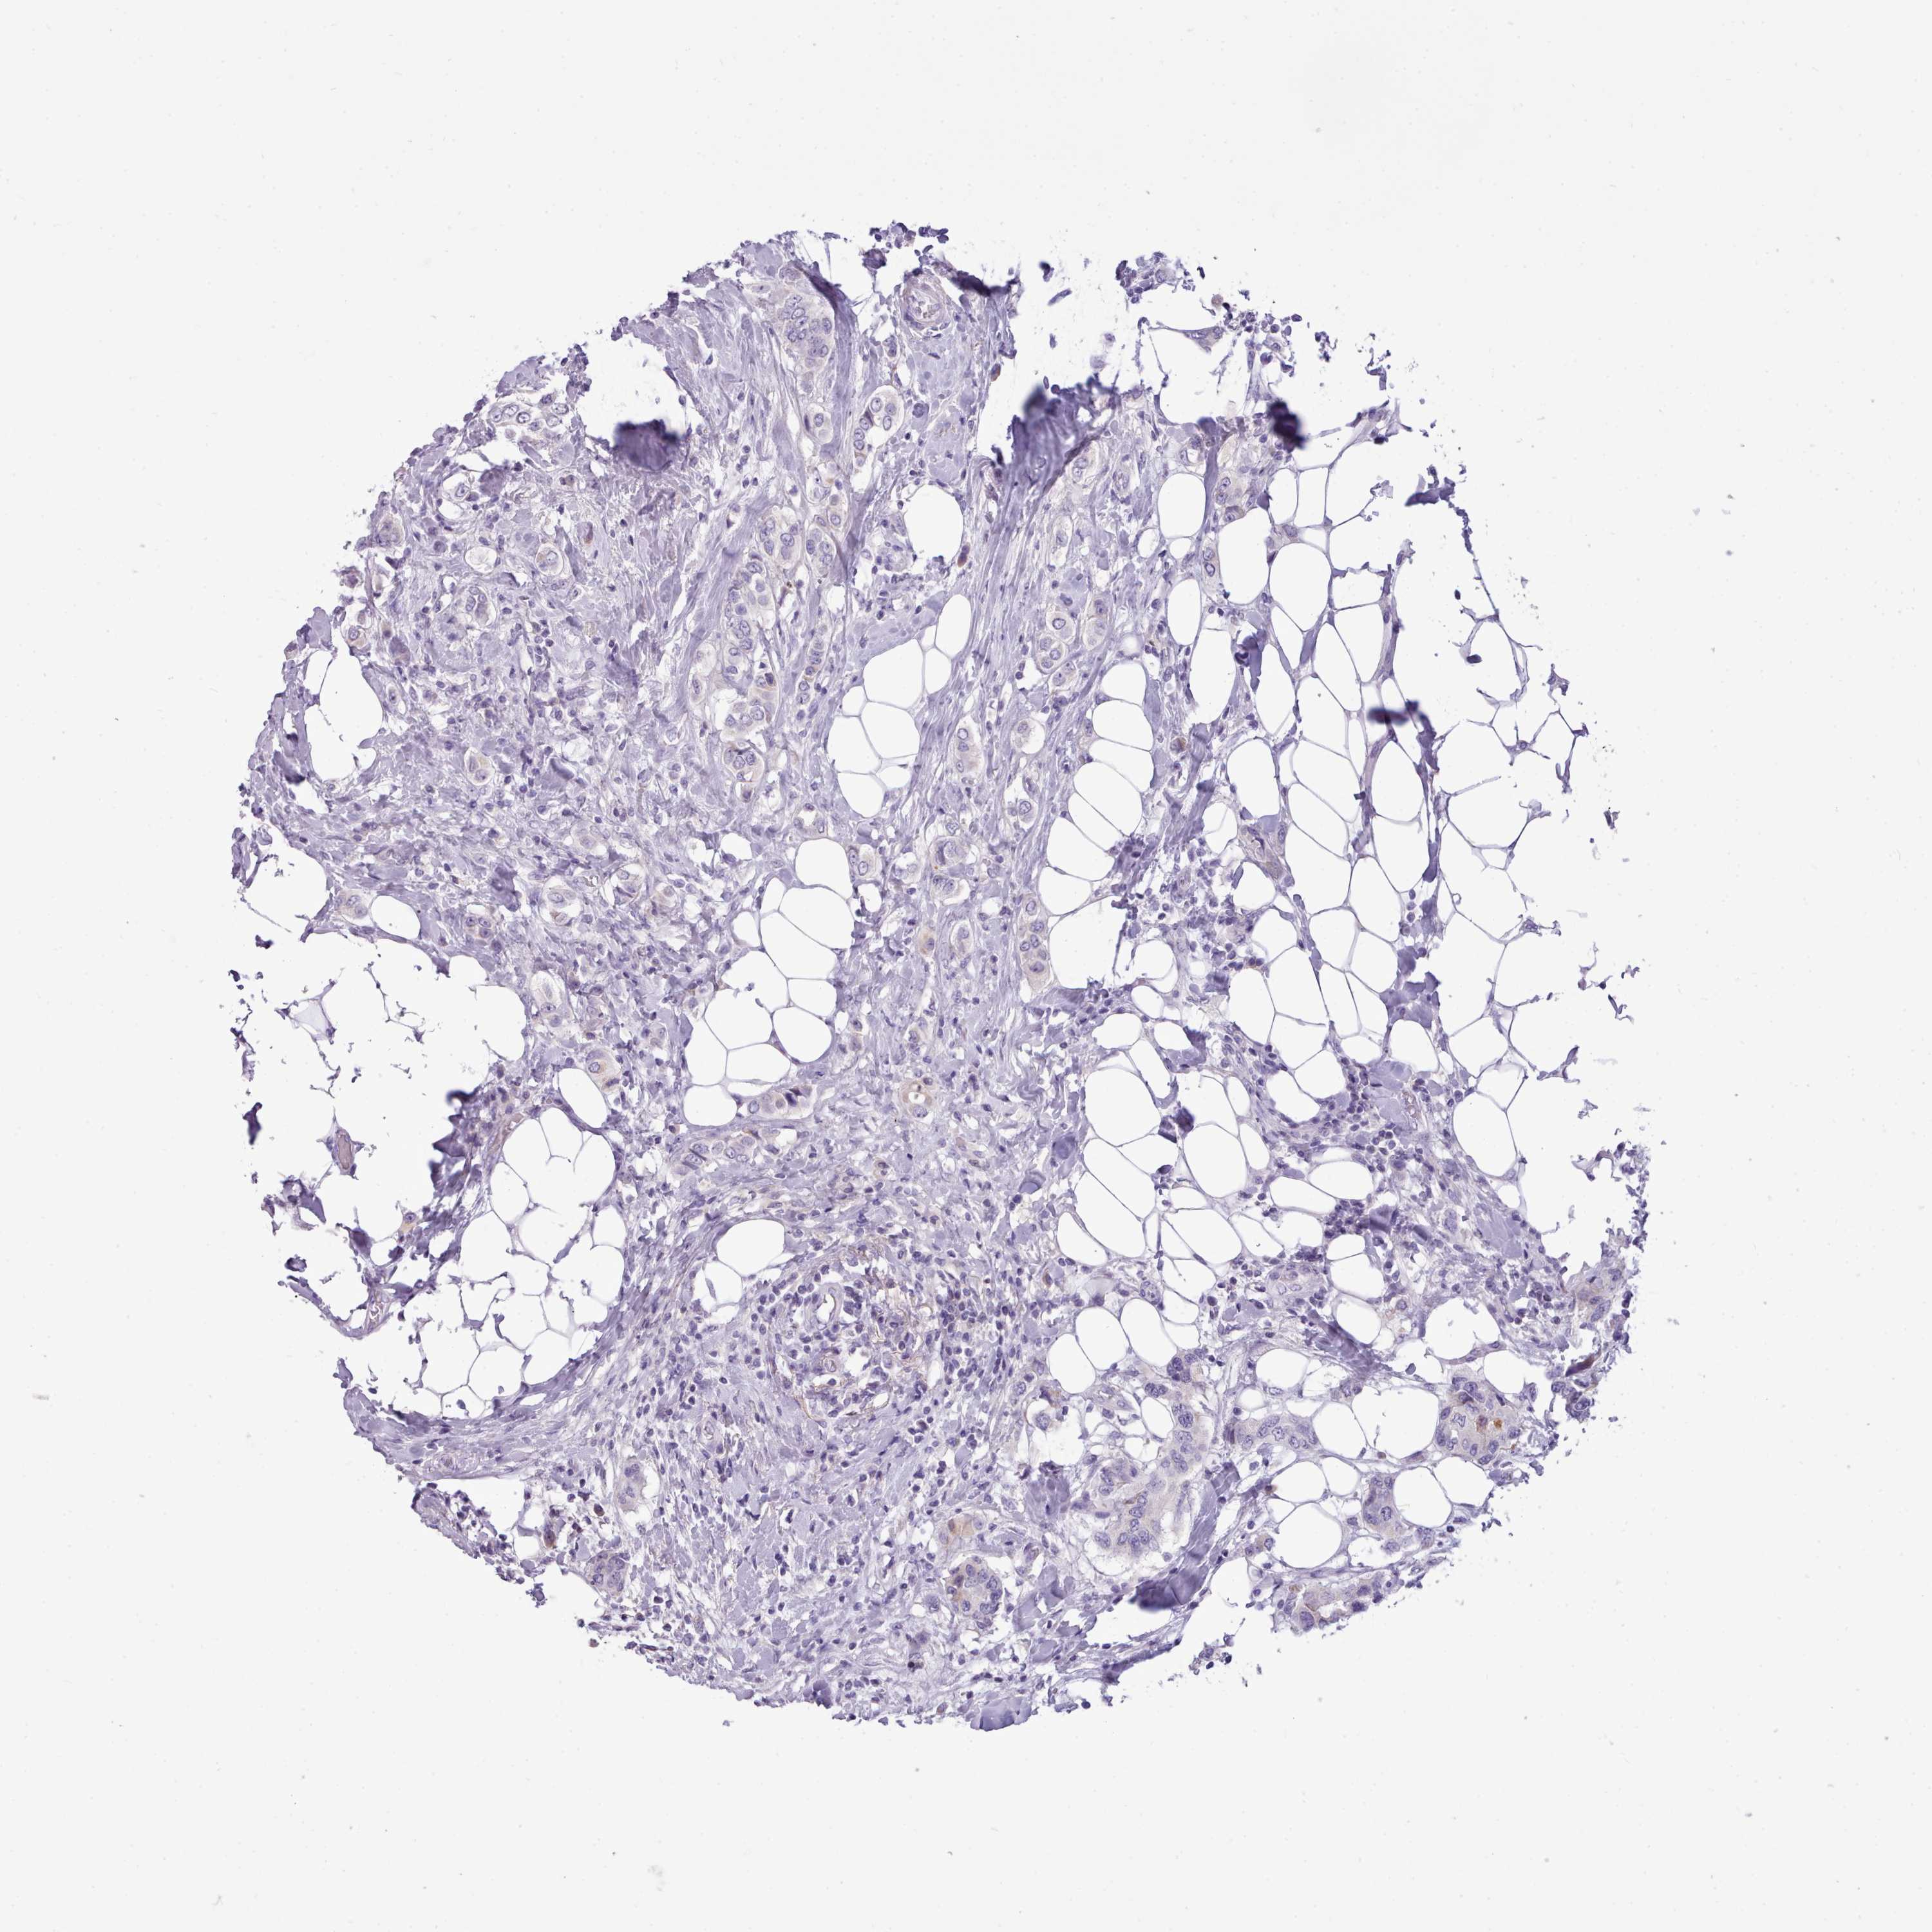

CANCER BREAST CANCER Show tissue menu

BRCA TCGA BRCA VALIDATION PROTEIN EXPRESSION

ANTIBODIES

AND

VALIDATION